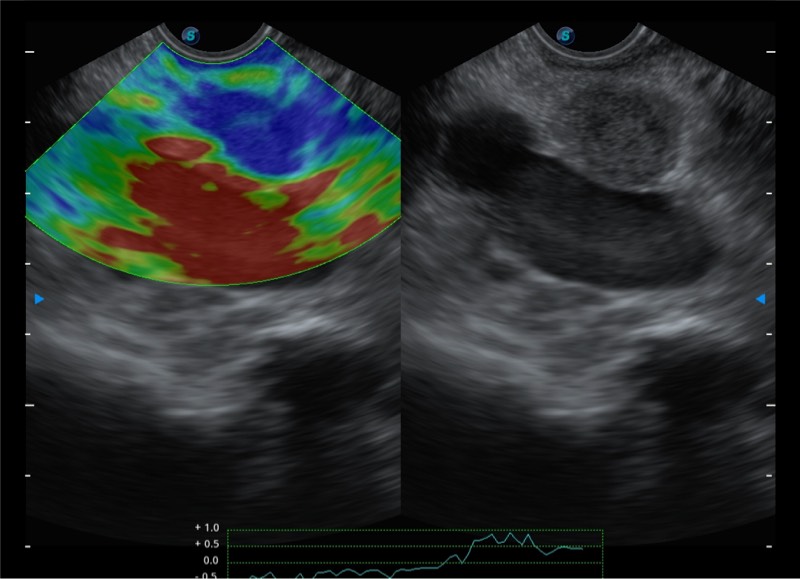

基于二十年的超声技术积累,九州酷游提供了最新一代的独立超声主机,在提供高质量图像的同时满足多学科使用。具备常见多普勒技术并提供弹性成像、声学造影等高端影像技术。新一代传感器具有更强的抗干扰能力并减少图像伪影。

4-12MHZ宽频输出